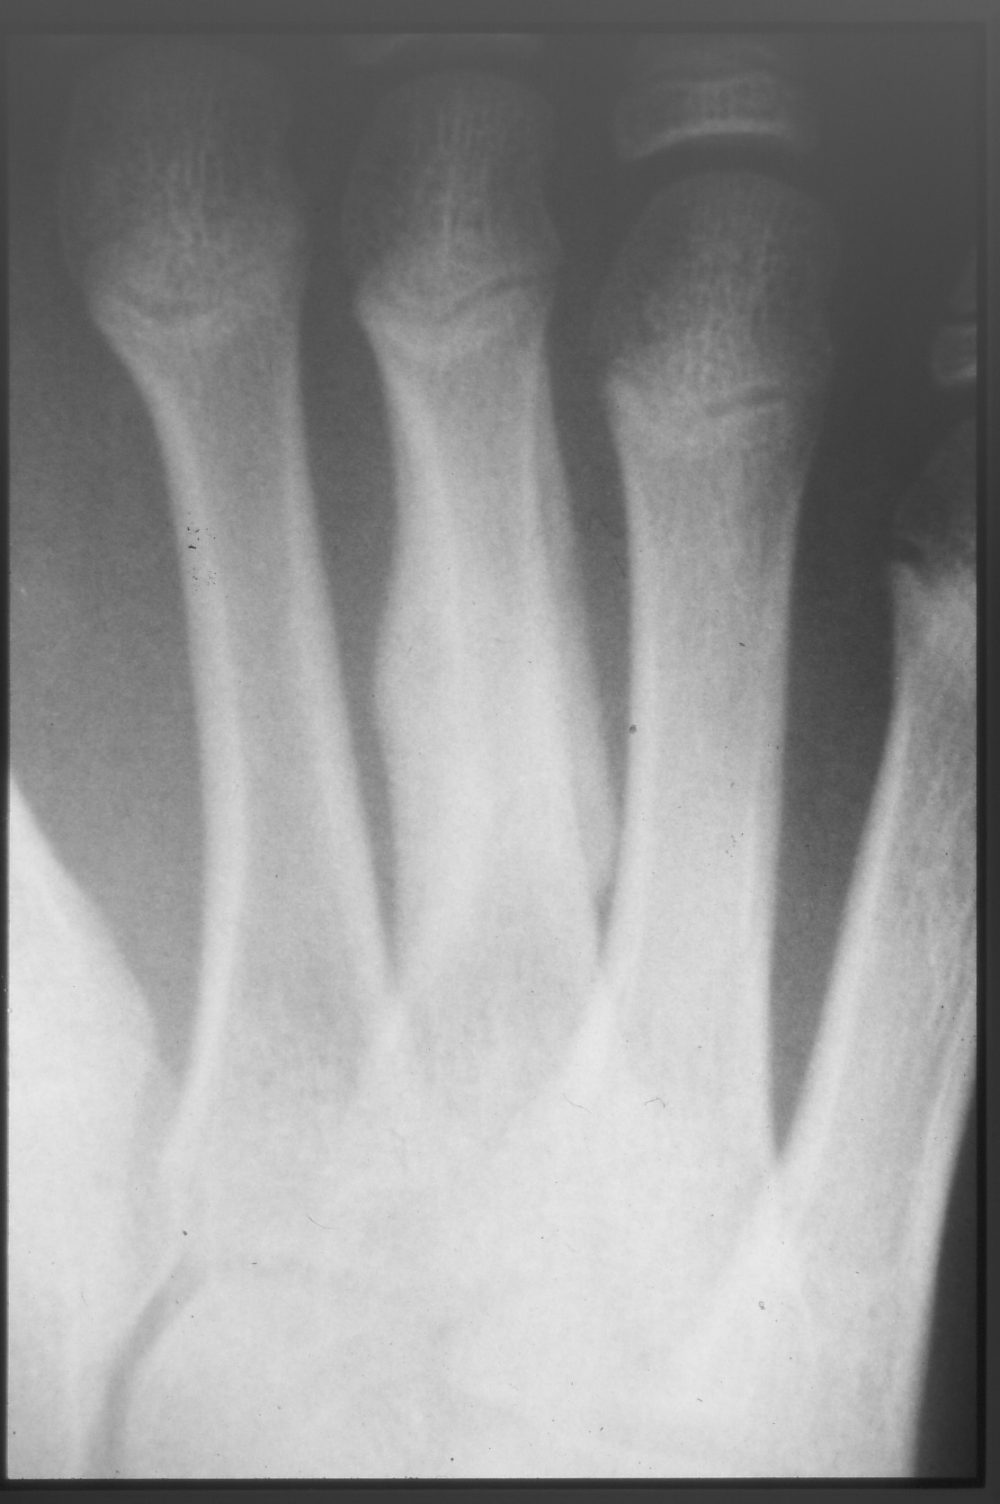

The symptom was relieved by rest from running for about 4 weeks. Play was gradually restarted from week 5, but complete recovery began at month 3. Bone formation was also good on X-ray at 3 weeks (Fig. 4) and 3 months (Fig. 5).

Figure 5 Three months after injury

Three months after the injury, the diaphysis has bridging (reinforcement) formation of the callus on both sides of the metatarsal bone, and the transverse diameter is about twice as thick. Healing is sufficient to resume play.